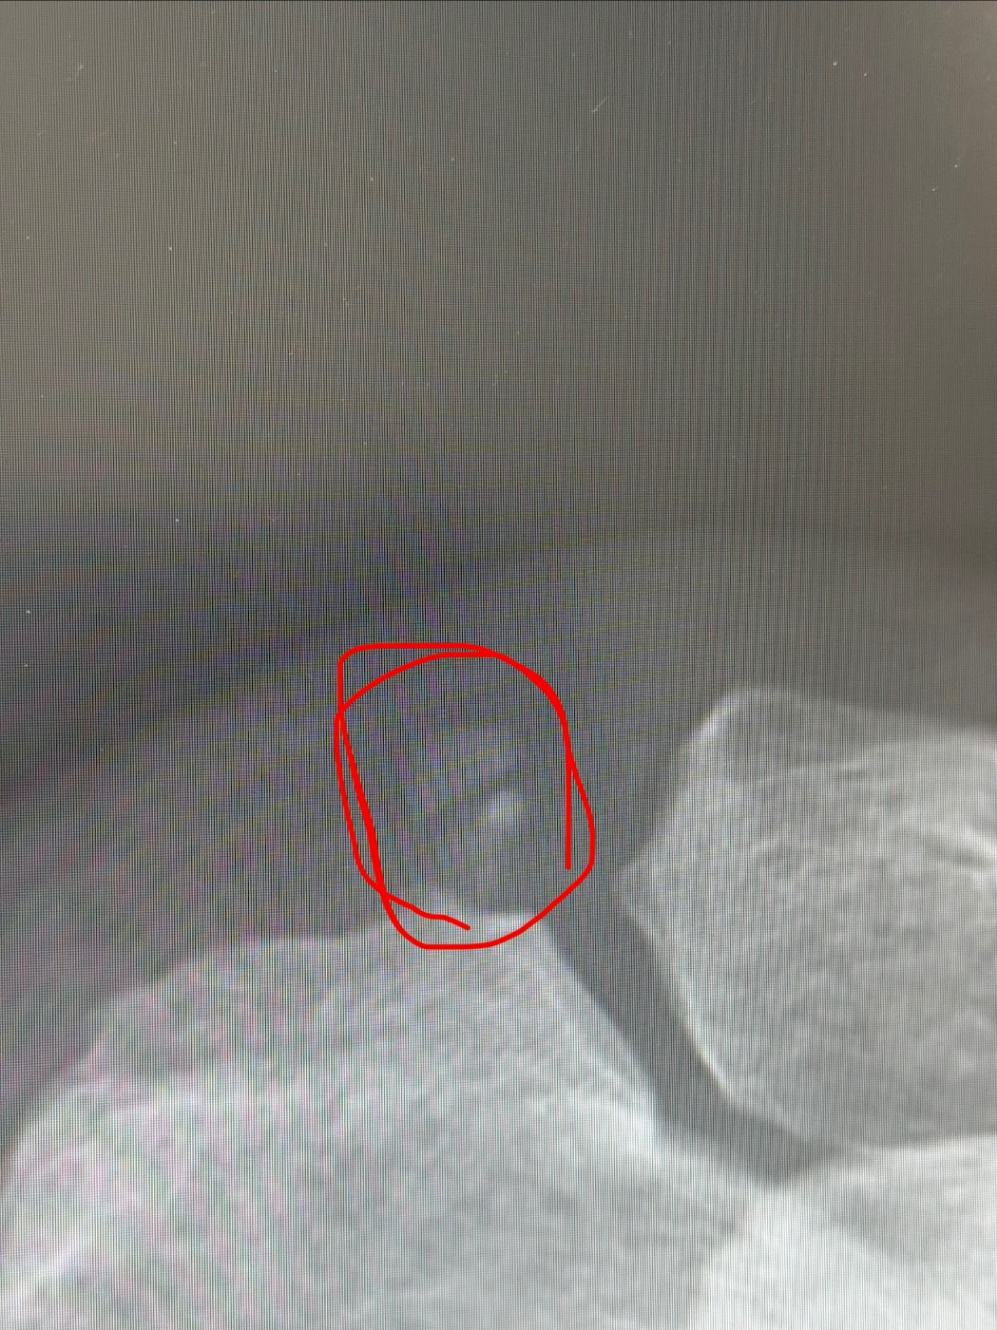

早速レントゲンを撮ったら、どうやら肩鎖関節という、肩甲骨と鎖骨をつなぐ関節のあたりに石灰ができているっぽかった。

石灰沈着性の関節炎は、後から知ったけど、ものすごい痛いらしい。レントゲンでわかる範囲だとこれだけで、石灰による炎症であればステロイド注射で炎症を抑えると言うこともできるけど万が一変な腫瘍みたいなものだと困るので、MRIいきましょうか、と、その場でMRI予約。家に帰って軽く昼飯食べて移動。武蔵小金井に移動。

結果、腫瘍とかはなく、肩の内側の骨や筋肉も特に問題のない状態だったので、最初のレントゲンでの結果通り「石灰沈着性の肩鎖関節炎」ということで確定。まあ良かったのか悪かったのか。